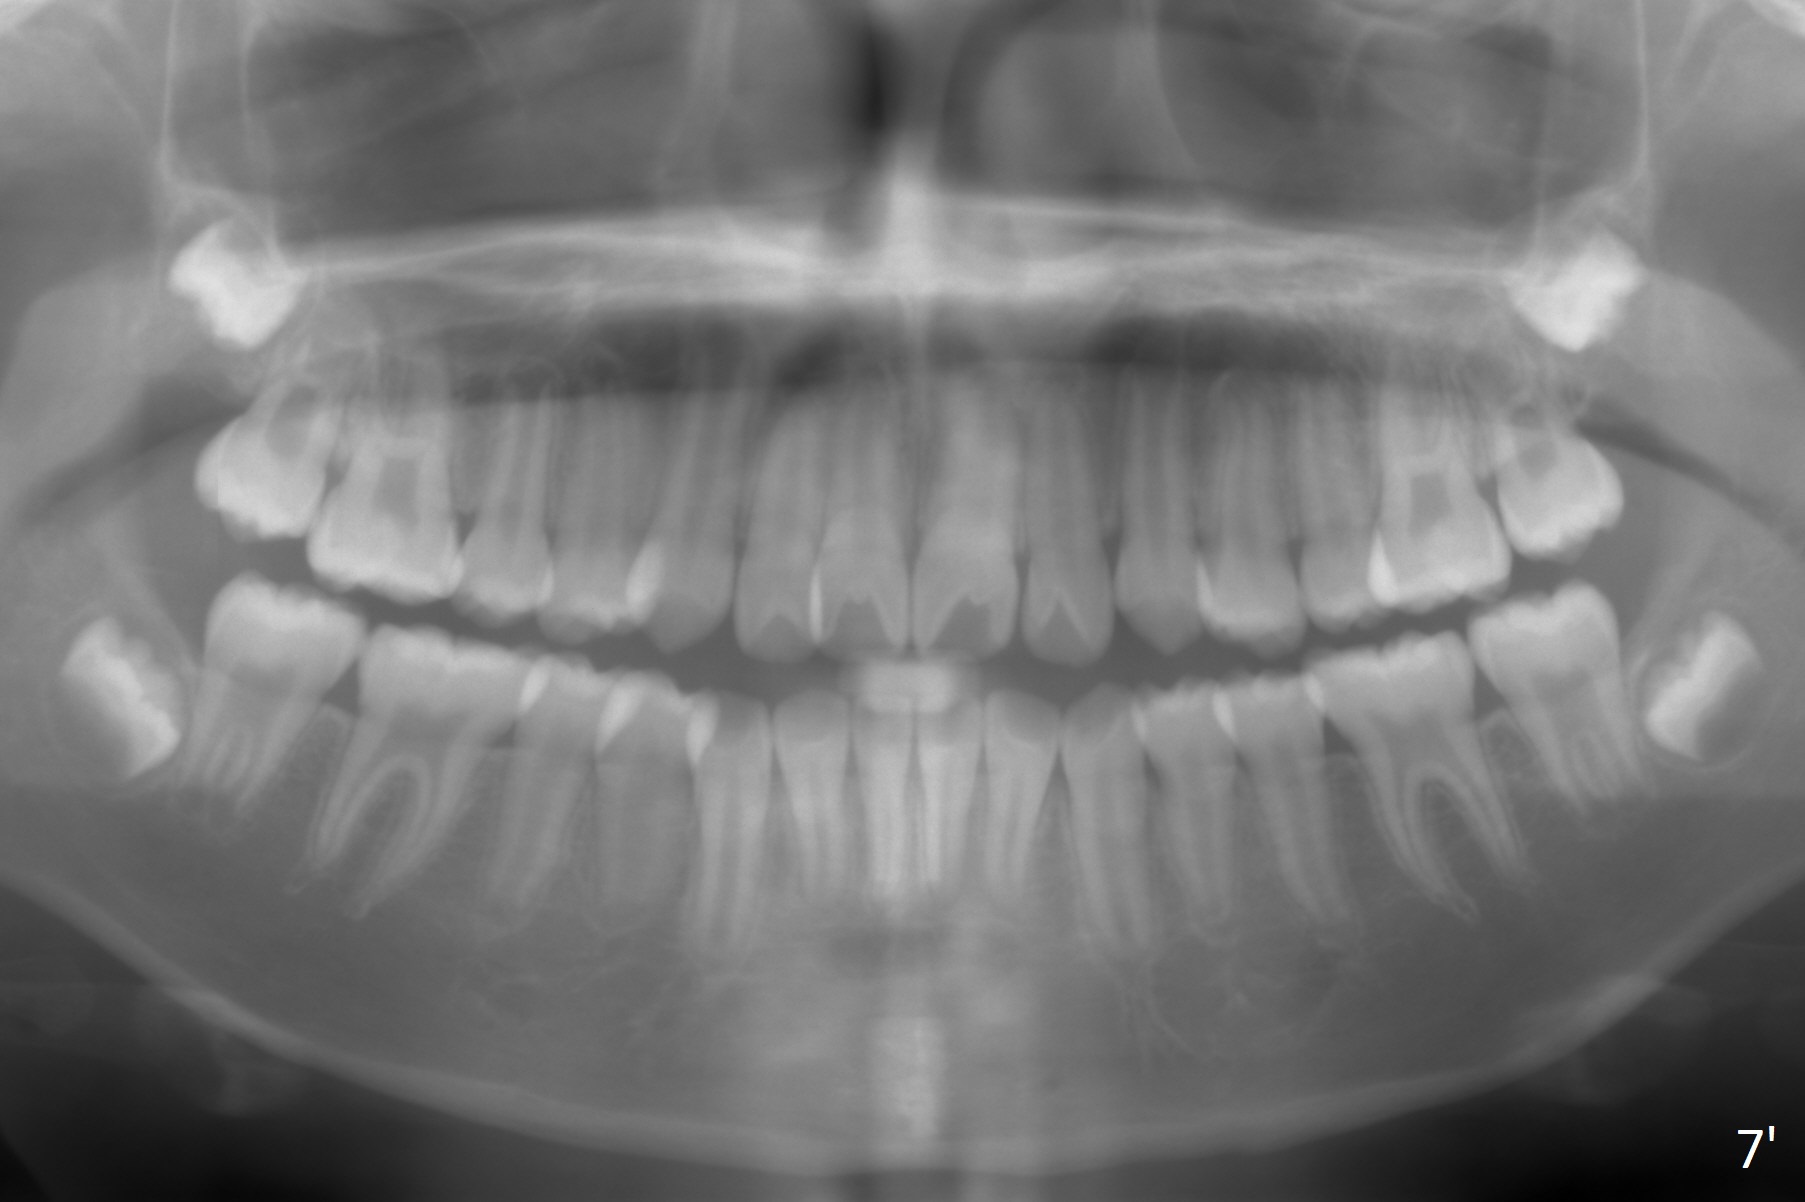

Two sisters (Sophia, 13 years old and Selina, 11) present to clinic for orthodontic treatment. Dental anomalies of Sophia include microdontia of the upper lateral incisors and congenital missing of the upper right permanent canine (Fig.5,6). For Selina, the upper right lateral incisor (Fig.5') and the upper left second bicuspid (Fig,6') are in cross bite.